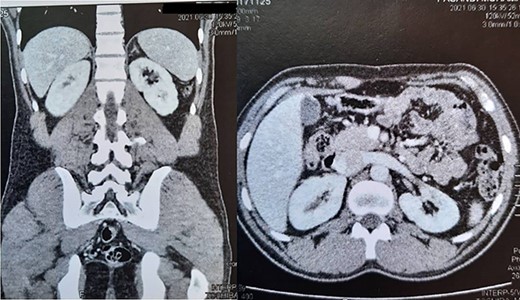

Surprisingly the mass enucleated without any difficulty and was removed uneventfully (Fig. 2). The warm ischemic time (WIT) was 30 min. A good rim of the normal kidney remained after mass resection. The renal defect was repaired with 4/0 vicryl on multiple rolls of surgical that anchored to the renal defect. In the follow-up, the renal function test was regular (Cr:1.2). The patient was discharged postoperative on the third day without any complications. The surgical pathology reported the solid-cystic mass (17 × 16 × 9 cm) as renal cell carcinoma (conventional type) with Fuhrman grade 2 and negative surgical margin. We followed up with the patient after surgery according to the standard imaging protocol in partial nephrectomy cases. Figure 3 depicts the last follow-up of the patient 7 years after surgery.